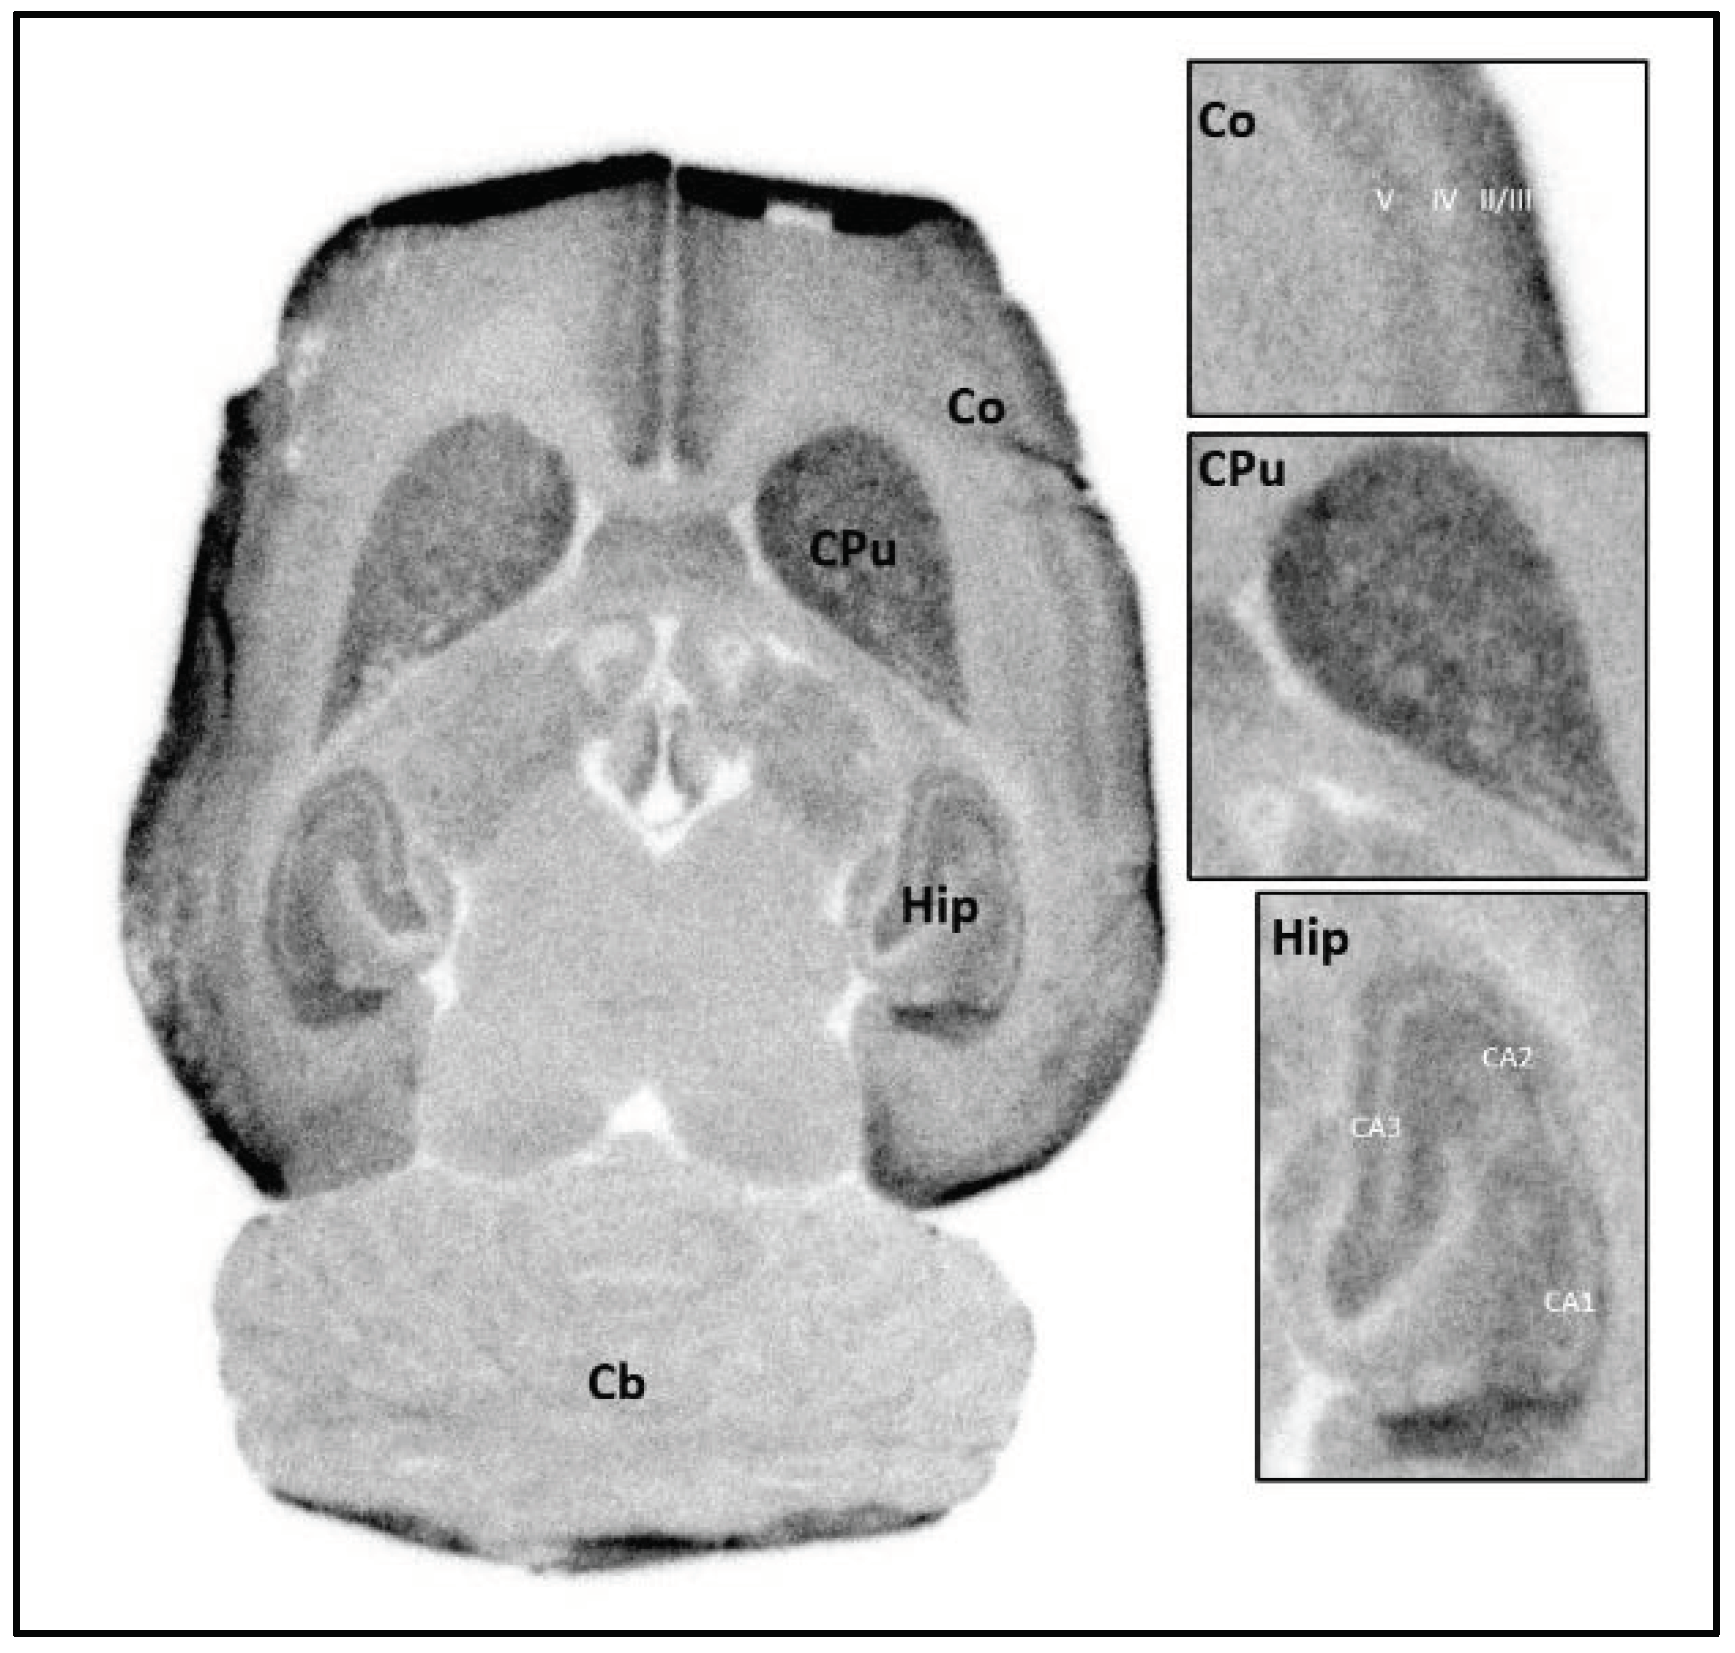

2.3.1. In Vitro Autoradiography with Rat Brain Cryosections

3.3.1. In Vitro Autoradiography